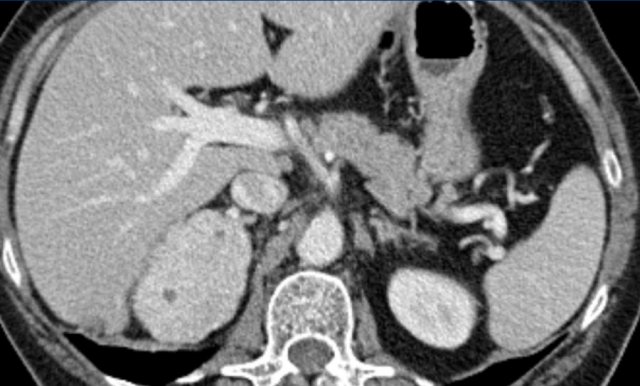

Pheochromocytomas

Pheochromocytomas (PCCs) are rare neuroendocrine neoplasms originating from the adrenal medulla. At presentation, these lesions commonly exceed 3 cm in diameter, with nonfunctioning tumors generally larger than hormonally active ones.

On noncontrast CT, PCCs typically demonstrate attenuation values >10 HU, which may be further elevated in the presence of hemorrhage.

Their rich vascular supply yields intense postcontrast enhancement.

While CT and MRI lack specificity in distinguishing PCCs from other adrenal masses, the clinical relevance of this limitation is mitigated, since only 10–20% of PCCs are asymptomatic, and biochemical screening via urinary and plasma metanephrine offers exceptional sensitivity (97–99%).

Given that all adrenal incidentalomas with unenhanced attenuation >10 HU require metanephrine testing, the vast majority of PCCs are reliably identified.

Large tumors are prone to hemorrhage and necrosis mimicking malignancy.

Image

Large PCC with central necrosis.